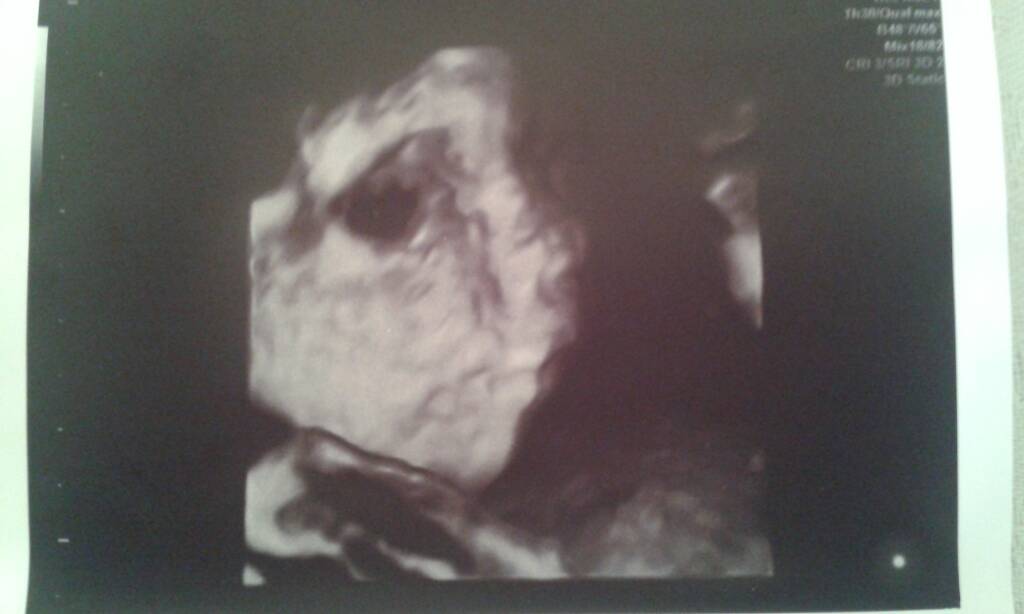

Uffff. Ewcia ale teraz przywaliłaś. Gratulacje!!!Dziewczyny przepraszam ale pol godz opoznilo sie bija dwa serduszka jedno slabiej sie rozwija za dwa tyg kolejne usg

Napisze z domu musze dojsc do siebie